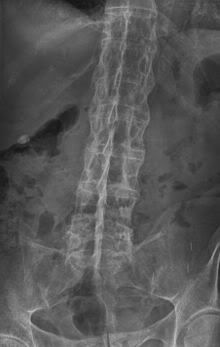

I thought that this would be helpful to those that are looking for answers or those that would like to see what radiographic evidence looks like and how it is defined... (a) T1-weighted and (b) short tau inversion recovery (STIR) magnetic resonance images of lumbar and lower thoracic spine in psoriatic arthritis. Signs of active inflammation are seen at several levels (arrows). In particular, anterior spondylitis is seen at level L1/L2 and an inflammatory Andersson lesion at the upper vertebral endplate of L3. The fourth, fifth and sixth vertebra contains certain peculiarities, which are detailed below. Radiology shows the appearance of "fluffy, new" bone or bridging/fusion.